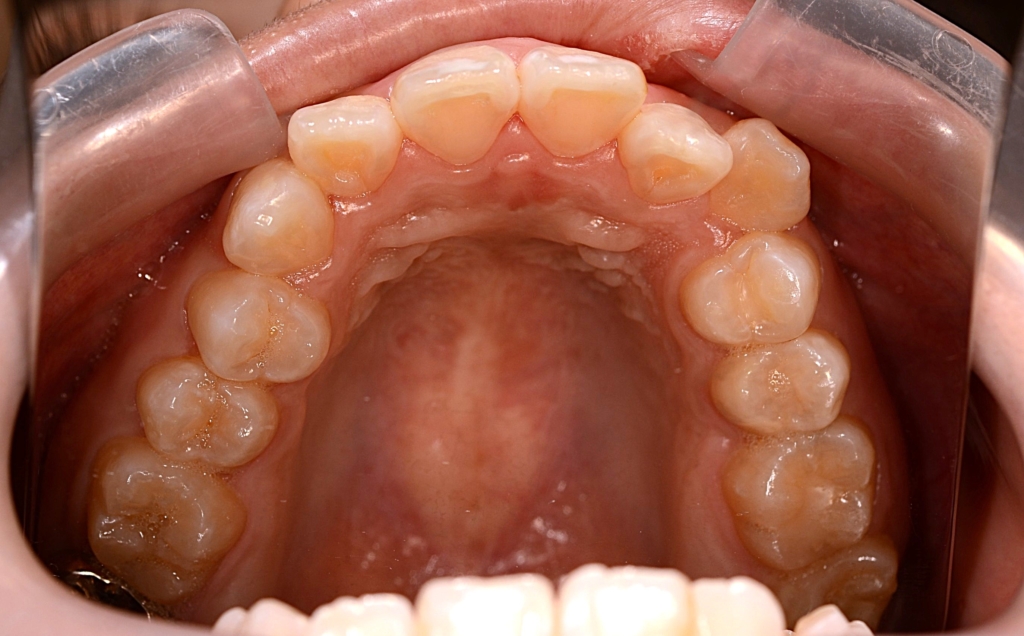

上下とも前歯がきれいに並んで、引っ込めるステップに入る目途がついたので、上の奥歯辺りにアンカースクリューを植立しました。

・上顎の口蓋の中央部に2本

・下顎の智歯を抜歯してその奥に1本ずつ(計2本)

上の歯列を更に後方へ移動させるためには、右上の埋伏した智歯が邪魔でした。

しかし、その歯は神経を取り、内部を大きく削り残った歯質が薄くなり弱くなっています。

さらに言うと神経を取る治療にステップで治療器具を折れ込ませてしまったようです。

普通なら埋伏している智歯を抜歯するのですが、今回、手前の奥歯の条件が悪かったので、あえて手前の差し歯になっている奥歯(赤い線で囲われた歯)を抜歯して、埋っている智歯(青い線で囲われた歯)を残して、将来萌出してきて咬合に参加する未来を期待することになりました。

上顎のアンカースクリューには、PLAS & 奥歯の内側にはパラタルバーを付けて